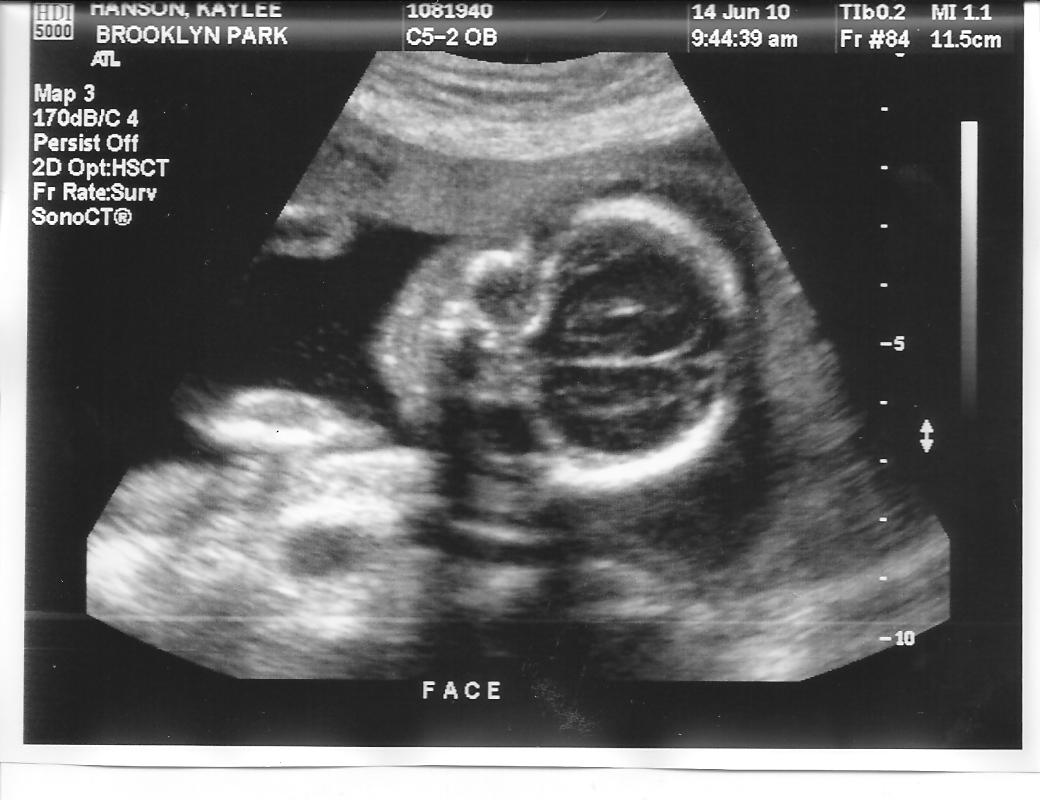

Next we have the "alien" shot (I TOLD you there was an alien in my belly!). This is a shot from above, looking at it's head. You can see it's big brain and then eyesockets, a little nose and if you look very carefully, a little tiny mouth:

The little blueberry was wiggling and squirming during the entire ultrasound. I think the nice technician woke it up from a little snooze and then it wanted to move around lots and lots. It was fun to see it moving on the screen and to be able to feel little kicks and punches in my belly at the same time!